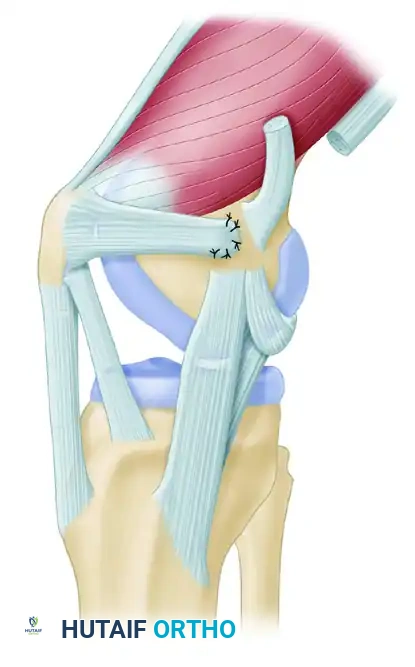

Patellofemoral instability is a complex, multifactorial pathology that demands a nuanced understanding of knee biomechanics, soft tissue restraints, and underlying bony morphology. The medial patellofemoral ligament (MPFL) is the primary passive restraint to lateral patellar translation, contributing 50% to 60% of the restraining force from 0 to 30 degrees of knee flexion. In cases of acute or recurrent lateral patellar dislocation, the MPFL is universally torn or attenuated.

Figure 47-14A: Medial patellofemoral ligament detached from the medial femoral epicondyle following an acute patellar dislocation.

Figure 47-14B: Medial patellofemoral ligament with the firm edge of the vastus medialis obliquus muscle reinserted to the periosteum of the medial femoral epicondyle, demonstrating an alternative adductor magnus harvest technique.

Surgical Approach and Soft Tissue Dissection

- Incision Options: Depending on patient habitus and surgeon preference, utilize either a single 4-cm longitudinal incision centered between the medial patella and the medial femoral epicondyle, or two smaller incisions (one at the superior medial patella and one at the adductor tubercle).

- Retinacular Exposure: Dissect subcutaneously to expose the proximal medial retinaculum at its insertion into the proximal half of the patella. Make a 1.5-cm vertical incision in the retinaculum.

- Extrasynovial Tunnel Creation: Using blunt dissection (e.g., Metzenbaum scissors or a curved Kelly clamp), carefully develop a plane between Layer 2 (the MPFL) and Layer 3 (the joint capsule). Direct the clamp toward the medial epicondyle. It is critical to stay extrasynovial to prevent intra-articular graft migration and synovial fluid leakage.

Closure and Postoperative Care

- Closure: Repair the medial retinaculum over the reconstructed MPFL using the reserved sutures from the patellar anchors. Close the subcutaneous layer with 2-0 absorbable sutures (e.g., Vicryl) and the skin with a subcuticular closure (e.g., Monocryl).

Figure 47-15E: Final subcutaneous and skin closure following MPFL reconstruction.